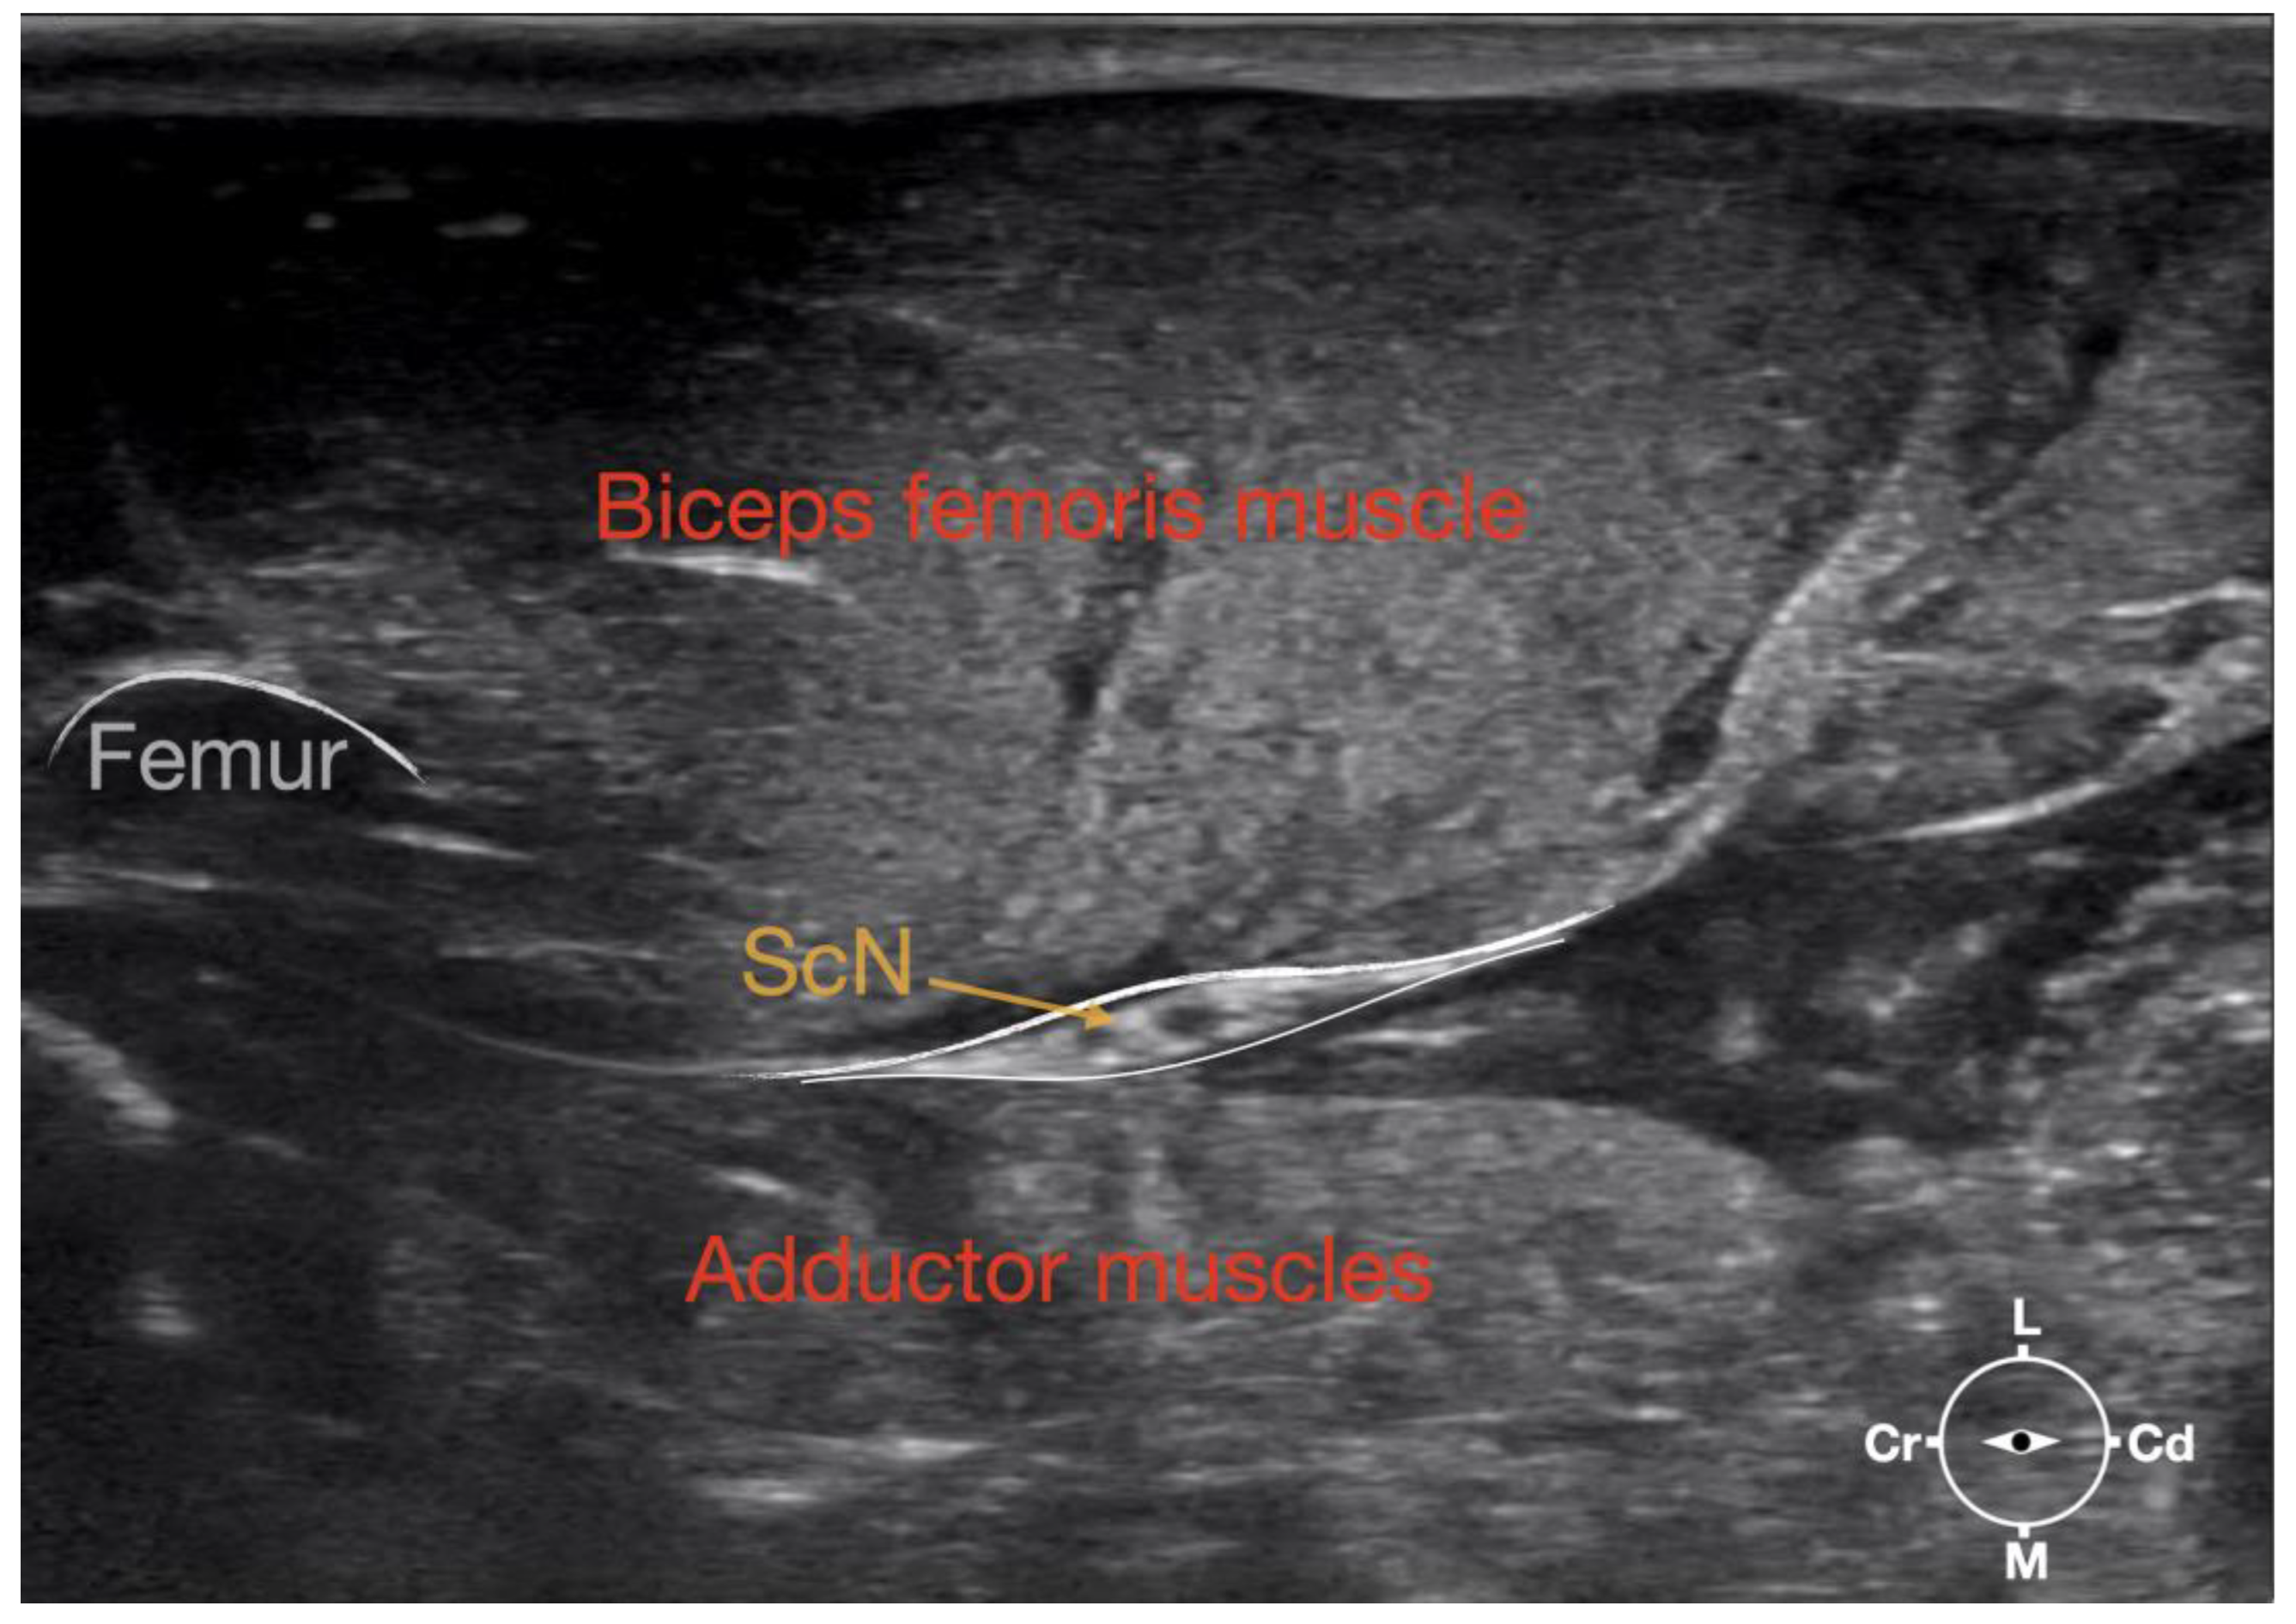

3.1.1. Sciatic Nerve

The ScN emerged between the greater trochanter of the femur and the sciatic tuberosity where its proximal muscular branch was detached from the hamstring muscles. The nerve continued in the distal direction to separate at the level of the distal third of the femur into the tibial and the peroneal nerve. Based on the anatomical dissection and US scans performed in this phase, the best level for injection was determined to be in the proximal third of the femur. At the level of the proximal femur, the sciatic nerve was located caudally to the femur, medially to the biceps femoris muscle, cranially to the semimembranosus, and lateral to the adductor muscles (Figure 7).

Ultrasonographically, the sciatic nerve appeared as a binocular structure with a hyperechoic rim surrounded by the muscular fascias of the biceps femoris and adductor muscles at this level. All muscles were displayed as structures with heterogeneous echogenicity. The biceps femoris muscle was lying lateral to the ScN while the adductor muscle was medial to the ScN. The femur was displayed as a hyperechoic structure with acoustic shadow and located cranial to the ScN nerve.